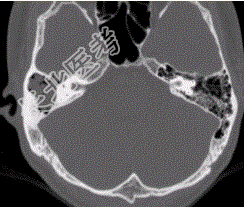

- [材料题] 患者男,25岁,右耳流脓液、听力下降5年。查体:右侧鼓膜穿孔,传导性耳聋,CT检查如下图。